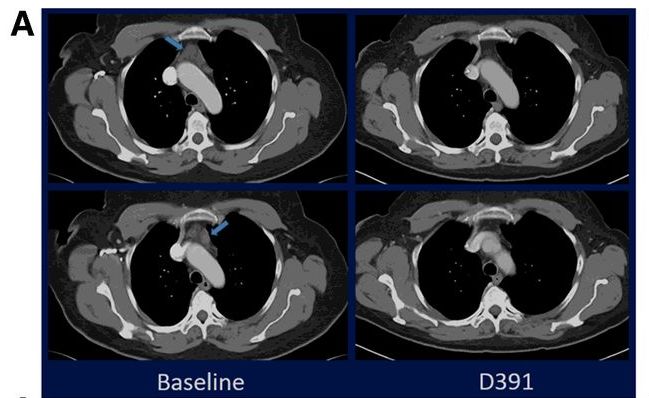

这位61岁的男性患有局部晚期错配修复缺陷型胰腺癌的患者,化疗后入组M7824的临床试验,治疗3个月的CT扫描显示部分缓解,4.5个月时仍显示部分缓解(30%),半年后CT扫描显示病灶竟缩小49%!CEA持续下降!